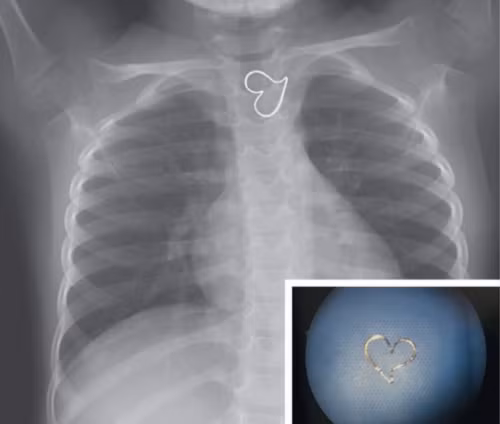

Hình trái tim trên ảnh chụp X-quang thực quản của một bé gái ba tuổi trông như được vẽ thêm vào, thực ra là mặt dây chuyền.

Theo Live Science, bức ảnh này được công bố mới đây trên tạp chí y học New England. Các bác sĩ tại Đại học California (Mỹ) cho biết bé gái ba tuổi được đưa vào phòng cấp cứu sau khi nuốt phải mặt dây chuyền màu vàng. Vì vậy, nhóm tác giả đặt tên ca bệnh là "trái tim vàng".

| Ảnh chụp X-quang của em bé ba tuổi. Ảnh: NEJM. |

Qua ảnh chụp X-quang, đội ngũ y tế xác định dị vật hình trái tim mắc kẹt trong thực quản bệnh nhi. Do mặt dây chuyền nằm yên một chỗ, các bác sĩ nội soi lấy nó ra cơ thể bé gái mà không cần phẫu thuật. Hiện bệnh nhi đã hồi phục và trở về nhà.